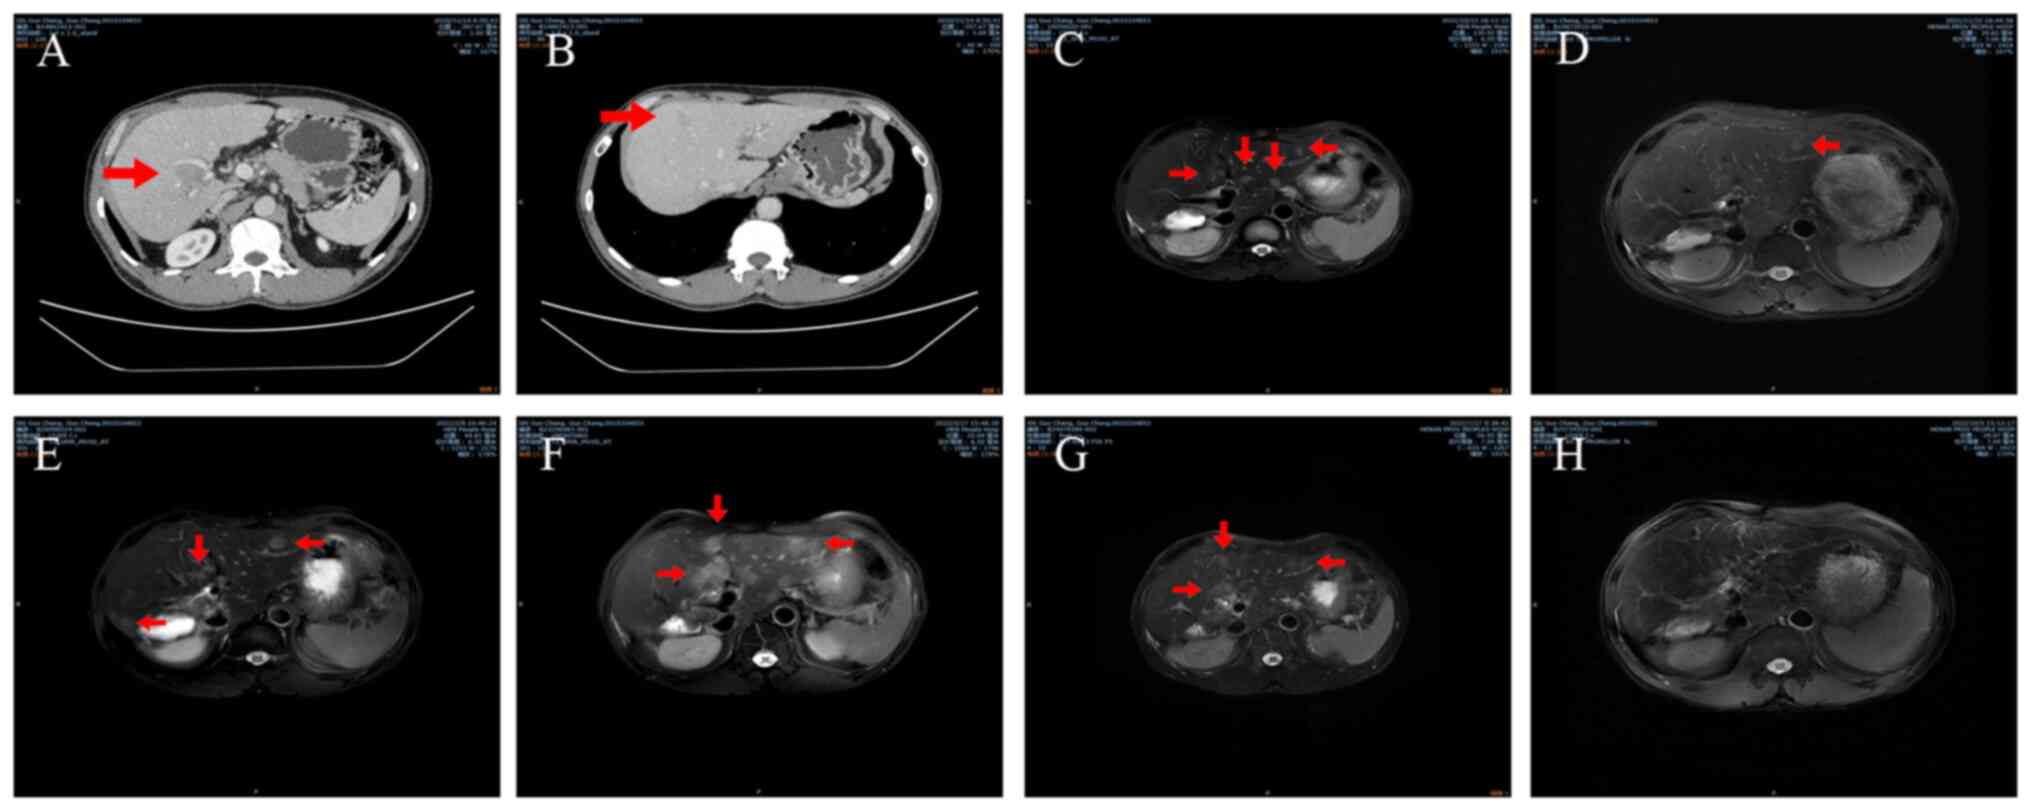

The patient was transferred to Henan Provincial People's Hospital (Zhengzhou, China) in November 2020 for further examination and treatment. The patient had been infected with hepatitis B virus a number of years prior and was not receiving any antiviral treatment at the time. The patient was diagnosed with HCC accompanied by intrahepatic metastasis and liver cirrhosis. Hepatitis B virus DNA level was 4.14x101 IU/ml, initial α-fetoprotein (AFP, reference value: 0-7 ng/ml) level was 9.86 ng/ml and their carbohydrate antigen 19-9 (CA199, reference value: 0-35 U/ml) level was 36.53 U/ml. CT performed at our hospital revealed neoplasms located in the right hepatic lobe and segment VIII (Fig. 1A and B). The performance status score of the patient was 0 and their Child-Pugh score was 5 (12,13). The tumor sizes were 2.1x2.2 and 1.8x1.9 cm. The tumor was defined as stage B according to the Barcelona Clinic Liver Cancer criteria and as stage IIA according to the China Liver Cancer Staging criteria (14,15).

A total of 11 months after the surgery in October 2021, magnetic resonance imaging (MRI) demonstrated multiple intrahepatic masses that were considered to represent recurrences (Fig. 1C). There was no notable increase in the AFP level (5.51 ng/ml) of the patient. Transarterial chemoembolization (TACE) was performed 3 days after MRI and treatment with anti-PD-1 antibody sintilimab (200 mg every 21 days.) injection was initiated 13 days after MRI. Dynamic contrast-enhanced perfusion MRI (2021-11) demonstrated that the disease had not progressed and the length of tumor (8.21 mm) had shrunk slightly based on Response Evaluation Criteria in Solid Tumors (RECIST). Therapy with lenvatinib plus anti-PD-1 was continued. A subsequent MRI scan in February 2022, demonstrated that the disease had progressed in terms of both size (6.74 mm) and quantity (3 distinct tumors) based on RECIST, as the tumor was larger compared with on the previous MRI scan (Fig. 1E). Because of this, lenvatinib was discontinued and regorafenib (Take 160 mg once a day.) combined with anti-PD-1 (200 mg every 21 days.) was administered instead, with TACE performed 2 days later in February 2022. Another MRI scan in May 2022 demonstrated that disease progression had occurred once again, in terms of both size and quantity, as the tumor was larger (15.56 mm) and there were more lesions (More than 6 distinct tumors) compared with the previous scan based on RECIST (Fig. 1F). The AFP level (reference value: 0-7 ng/ml) of the patient had also increased to 84.59 ng/ml and their VEGF level (reference value: 0-160 pg/ml) had increased to 201.46 pg/ml. A second TACE procedure was performed in May 2022. Imaging and laboratory results demonstrated that the disease was resistant to regorafenib and anti PD-1; however, the regimen remained unchanged. Another MRI scan in July 2022 demonstrated that the mass had not notably changed since the previous scan (Fig. 1G). Although the AFP (39.97 ng/ml) and VEGF (154.82 pg/ml) levels of the patient had slightly decreased and the tumors appeared smaller than before, their numbers had increased (More than 8 distinct tumors) notably. It was therefore considered that the disease was resistant to regorafenib combined with anti-PD-1. The patient was then administered lenalidomide (Take 25 mg once a day.) and lenvatinib (Take 8 mg once a day.). An MRI scan performed after this in October 2022, demonstrated that the size of the mass had notably decreased (Fig. 1H), indicating that the patient had achieved a partial response. By January 2023, the AFP levels of the patient fell to 53.43 ng/ml and their VEGF level increased to 236.14 pg/ml compared with result in July 2022, and the patient reported no particular discomfort. The patient refused a follow-up MRI; however, according to their AFP levels and clinical manifestations the patient had been in a stable disease state for nearly 6 months (Last follow up: January 2023). The treatment timeline of the patient is summarized in Fig. 2.